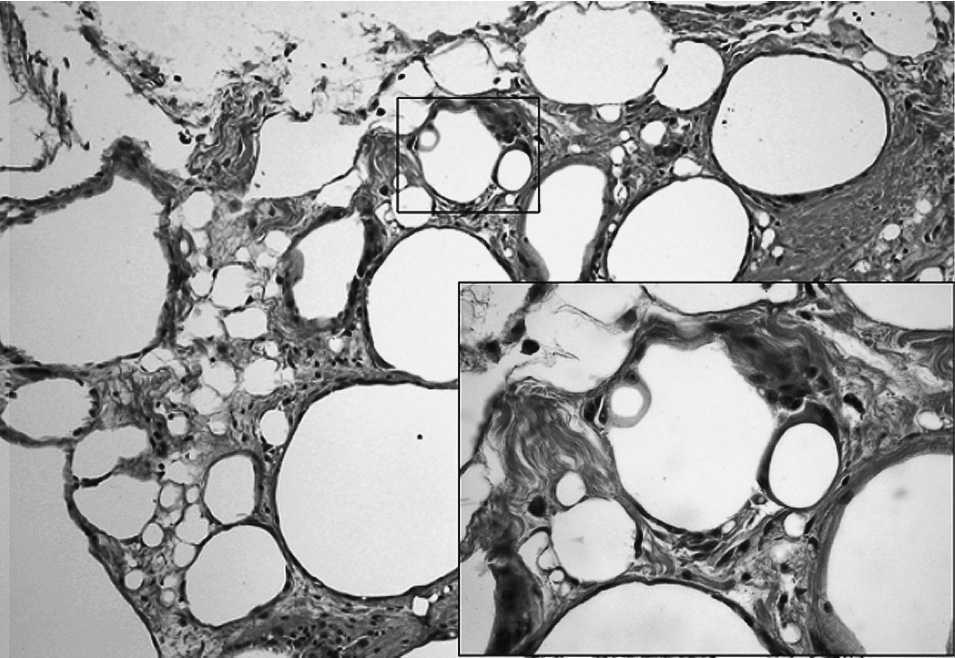

Las piezas quirúrgicas, tanto en la superficie externa como al corte seriado, mostraron múltiples cavidades quísticas, con contenido oleoso translúcido, entremezclado con el tejido adiposo mamario (fig. 3), así como restos fibrosos de localización retroareolar. De la cola axilar se aislaron entre 2 y 5 ganglios linfáticos. Microscópicamente entre los lóbulos grasos aparecía un gran número de cavidades quísticas delimitadas por una única banda de células de tipo inflamatorio (fig. 4), principalmente macrófagos y abundantes células gigantes multinucleadas de cuerpo extraño, aplanadas y en algunas áreas acompañadas de una banda de fibrosis sin otras células acompañantes. En el citoplasma de los macrófagos se observaron múltiples vacuolas, que en ocasiones contenían una pequeña cantidad de materia refringente, así como múltiples áreas de necrosis grasa. El parénquima mamario no mostró alteraciones relevantes. En los ganglios axilares se observaron depósitos materiales intracelulares o extracelulares, preferentemente en el seno subcapsular, similares a las descritas en el parénquima mamario.

Fig. 4. Imagen microscópica: vacuolas con pequeña cantidad de tejido refringente en el interior de los macrófagos.